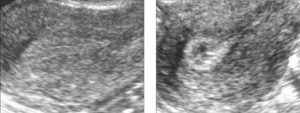

Во время УЗИ врач сканирует эндометрий, выявляя его толщину и структуру, которые должны соответствовать фазе менструального цикла, также врач оценивает эхогенность внутреннего слоя матки и его звукопроводимость. Также диагност отмечает новообразования в матке, их локализацию и размеры.

В первые дни цикла эндометрий на ультразвуковом исследовании отображается в качестве неоднородной структуры толщиной до 1 сантиметра; эхогенность слоя понижена, а звукопроводимость наоборот повышена.

- Аденомиоз: представляет собой кисты из эндометрия, образованные в миометрии (мышечном слое матки). При такой патологии миометрий на УЗИ выглядит как неоднородная структура с гипоэхогенными включениями.